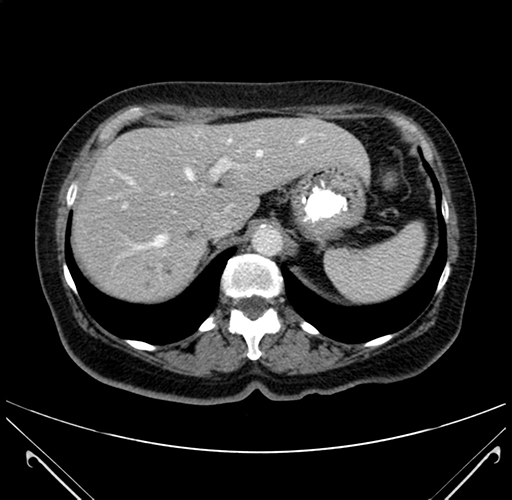

Pre-Chemo: Axial Venous

Axial Venous